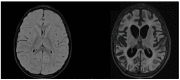

Subacute sclerosing panencephalitis (SSPE) is a late complication of measles virus infection that occurs in previously healthy children. This disease has no specific cure and is associated with a high degree of disability and mortality. In recent years, there has been an increase in its incidence in relation to a reduction in vaccination adherence, accentuated by the COVID-19 pandemic. In this article, we take stock of the current evidence on SSPE and report our personal clinical experience. We emphasise that, to date, the only effective protection strategy against this disease is vaccination against the measles virus.